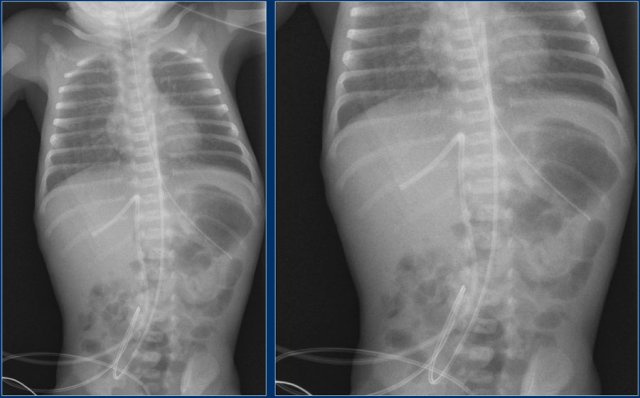

Umbilical venous line (7 )

Study the images.

Then continue reading.

The findings are:

• The umbilical venous line is too deep.

The line probably went through a patent foramen ovale and through the left atrium into a pulmonary vein.

In this patient ultrasound detected a thrombus in the left portal vein after umbilical venous line (arrows).

Catheter malposition in the left portal vein increases the occurrence of portal venous thrombosis.

Clinically silent portal venous thrombosis is frequently associated with catheterization of the umbilical vein in critically ill neonates, and spontaneous resolution without any treatment is expected in many cases.

Umbilical venous line (8 )

• The umbilical venous line is too deep

• After repositioning the tip is in a good position.

Notice that the endotracheal tube is too deep.